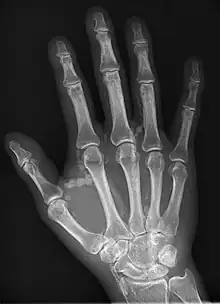

Oblique hand radiograph showing tumoral calcinosis

Oblique radiograph of the right hand demonstrating soft tissue calcification, characteristic of dialysis related metastatic calcification.